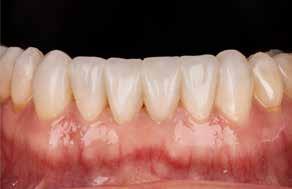

Fig. 5. A, B. Smil og kæbeforhold før og efter. Et bredere smil med korrektion af de laterale mørke rum. C-F. Harmonisk hældning af overkæbe- og underkæbeincisiver, rekonstruktion af den tabte tandsubstans efter nivellering af gingivaniveau og optimal bukko-lingval placering til direkte plastbehandling.

5. A, B. Smile and jaw relationships before and after. A wider smile with correction of the lateral dark spaces. C-F. Harmonious inclination of the upper and lower jaw incisors, reconstruction of the lost tooth substance after leveling the gingival level, and optimal bucco-lingual positioning for direct plastic treatment.